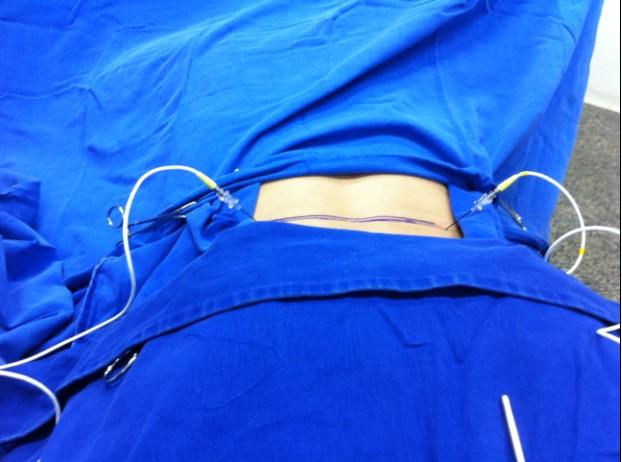

Ao lado, exemplo de IDET com acesso bilateral.

Uma das vantagens da Nucleoplastia é que ela é realizada de forma minimamente invasiva, geralmente sem a necessidade de incisões ou suturas. O procedimento é realizado em regime ambulatorial, o que significa que o paciente pode retornar para casa no mesmo dia da intervenção.